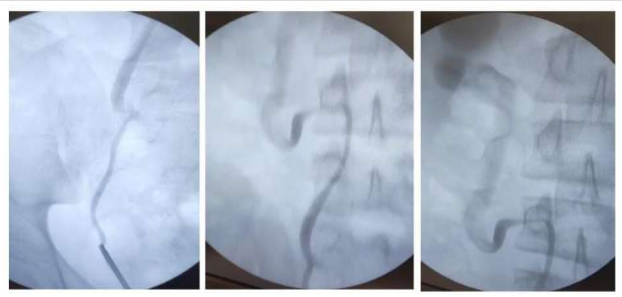

The distal ureter was not clear in the CT scan, because of this I performed a cystoscopy with retrograde Ureterography.

Next, I performed the operation through a right flank incision. I first exposed the ureter, then severed it, completely mobilized it, and redirected it from behind the inferior Vena Cava.

After spatulation of both ureter ends and insertion of a DJ stent, I completed an end-to-end anastomosis.